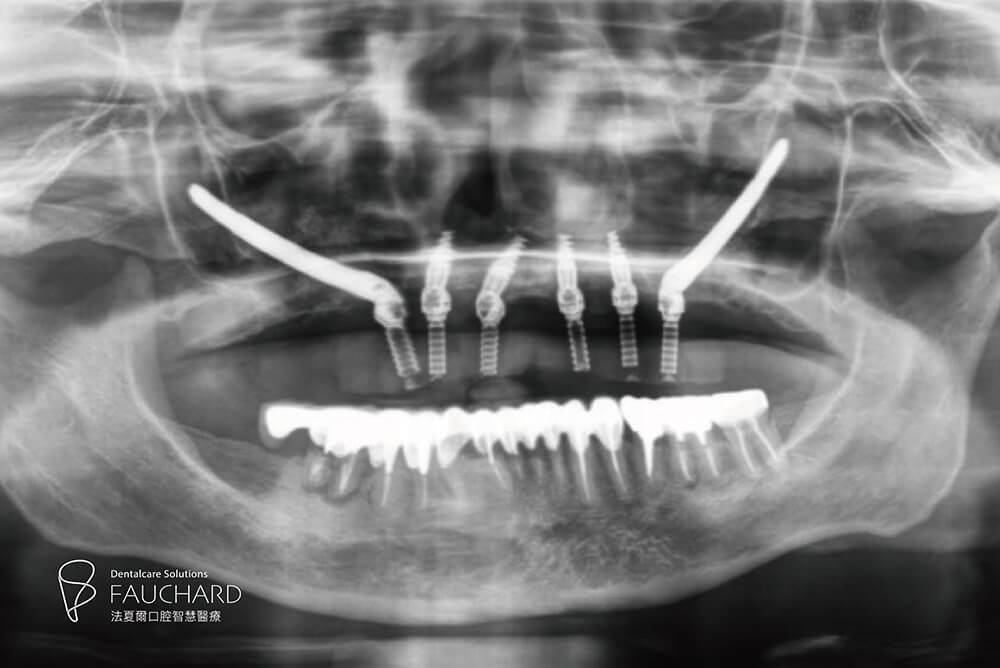

骨質不好的患者,也可選擇All-on-4 全口重建嗎?的確,All-on-4 全口重建的傾斜植體需植入良好骨質才能確保整體牙齒穩固,不過別擔心,當顎骨流失或缺損使得植牙困難,我們還有 Zygomatic implant 顴骨植體這項秘密武器!

Zygomatic implant 顴骨植體治療以更長更強壯的植體,跨過萎縮骨質區植入顴骨,給予假牙穩定支撐力。如此一來,儘管患者骨質條件不佳,也能接受 All-on-4 全口重建治療。

Zygomatic implant 顴骨植體,以顴骨固定植體,是高難度全口重建手術。

顴骨植體 All-on-4:

植體固定在骨質密度更高的顴骨。

● 口腔狀況:上顎無牙

● 治療時間:當天有牙

● 植體數量:6 根 (4根植體+2根顴骨植體)

● 假牙類型:上顎、整座固定假牙